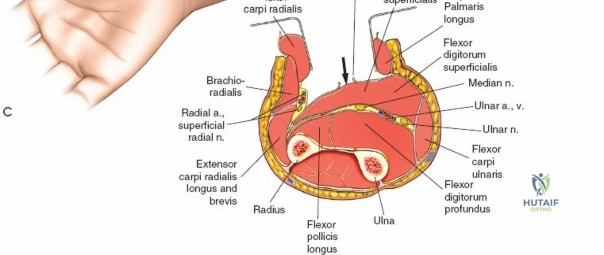

The anterior approach to the radius is an elegant example of utilizing true internervous planes to achieve deep exposure without denervating musculature. Distally, the internervous plane lies between the brachioradialis muscle (innervated by the radial nerve) and the flexor carpi radialis muscle (innervated by the median nerve). Proximally, the plane transitions to lie between the brachioradialis (radial nerve) and the pronator teres muscle (median nerve). Exploiting this plane allows the surgeon to mobilize the entire lateral muscular compartment (the "mobile wad" comprising the brachioradialis, extensor carpi radialis longus, and extensor carpi radialis brevis) away from the anterior flexor compartment.

Vascular Anatomy and the Recurrent Radial Leash

To confirm the correct plane, look for the superficial branch of the radial nerve. This sensory nerve runs on the undersurface of the brachioradialis muscle. Once the true medial edge of the brachioradialis is found, develop the plane between it and the pronator teres (proximally) or the flexor carpi radialis (distally). Retract the brachioradialis laterally, taking care to keep the superficial radial nerve attached to its undersurface to protect it from traction injury.